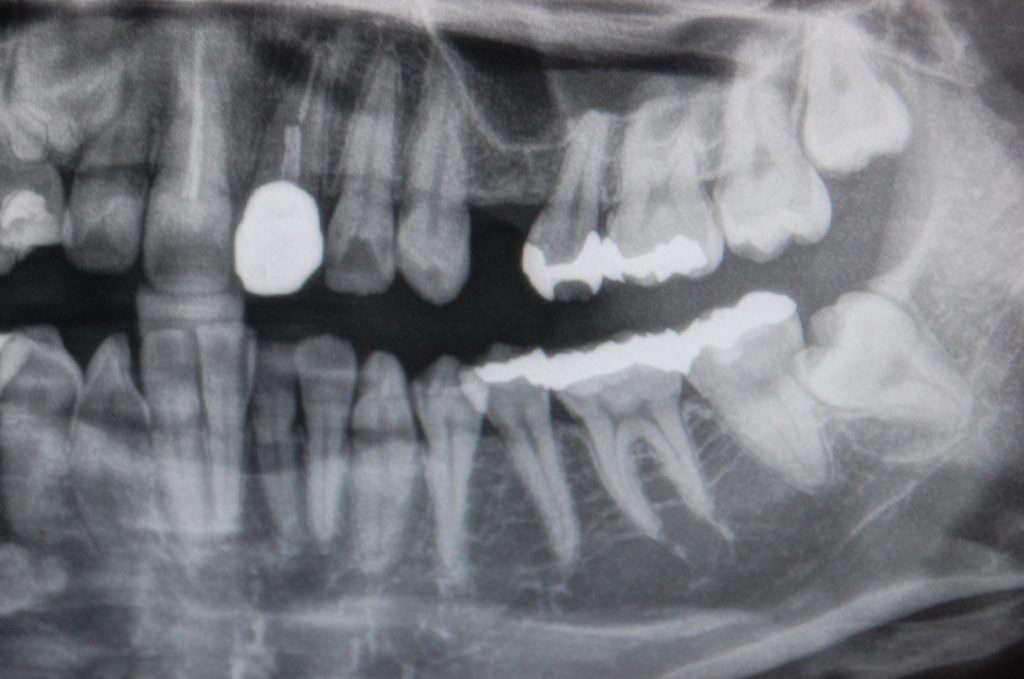

- 【症例】他院で断られたインプラント治療を、ソケットリフトによるインプラント埋入法で可能に

当患者様は他の歯科医院にて抜歯をされました。その医院でインプラントを希望されましたが、インプラントはできないとのことで、当院に相談に来られました。

ソケットリフトによりインプラントを埋入しました。

この患者様の場合、インプラントを埋入する骨の高さが不足していました。そのため、口腔内より上顎洞粘膜の挙上(ソケットリフト)を行いました。

【上顎洞粘膜の挙上(ソケットリフト)】

インプラントを埋入する箇所の骨が足りない場合で、骨の厚みが3~5ミリ以上ある場合に行います。

歯を抜いた部分から上顎の骨に穴を開け、骨移植をしてからインプラントのネジ部分を埋入します。この状態で3か月ほど待ち、人工歯を装着します。

インプラント埋入4ヶ月後に上部構造(ジルコニアクラウン)をセットしました。

今回の症例は、他歯科医院では不可能と断られたインプラント埋入でしたが、当院では難しい処置ではありませんでした。患者様の既存の骨が比較的残っていたため、簡単な上顎洞挙上(ソケットリフト)で済み、通常のインプラント手術と変わらない処置で対応できました。